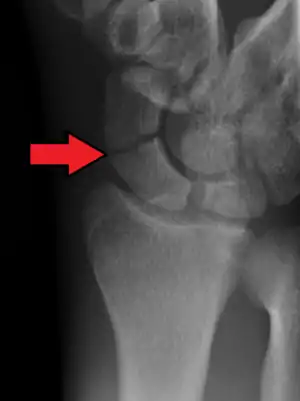

A subtle scaphoid fracture

A more obvious scaphoid fracture on a scaphoid view X ray

Radiolucency around a 12 days old scaphoid fracture that was initially barely visible.[12]